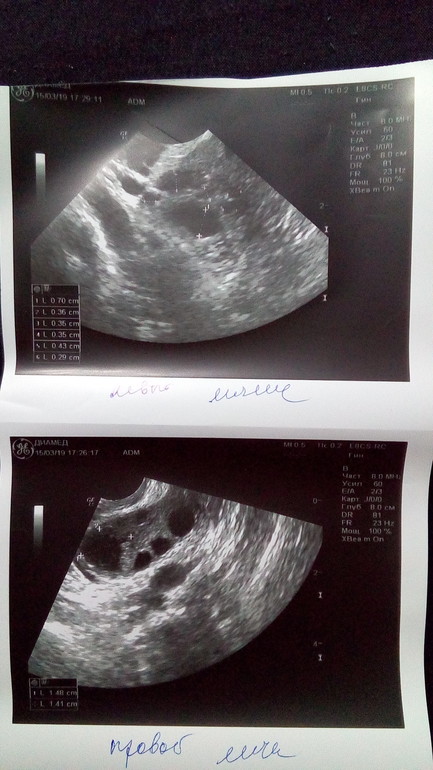

Фолликулометрия на 13 дц

УЗИ на 13 дц:

Эндометрий 10 мм

Свободная жидкость в позадиматочном пространстве в обьёме 10 мл

В ЛЯ 6 фолликулов: 3 мм, 3 мм, 3 мм, 3 мм, 4 мм, 7 мм

В ПЯ 7 фолликулов: 3 мм, 3 мм, 4 мм, 5 мм, 5 мм, 5 мм, 6 мм и ЖТ 15*14 мм

Узистка странно как то намерила ЖТ, она сама сказала, что размер указала внутри, а так оно больше.

Я попробовала измерить линейкой и оно около 20 мм вместе с жёлтым ободком.

Какой размер ЖТ считается правильным внутренний или полный?

P.S. Я уж поняла что на фото единица измерения другая, 1 см приравнивается к 1,3 см, вот она и разница видна. Значит всё правильно она померяла, внутренний диаметр ЖТ 15*14 мм, подрастёт ещё, надеюсь. На линейке 21 мм, а на самом деле 15 мм. Масштаб не 1:1.